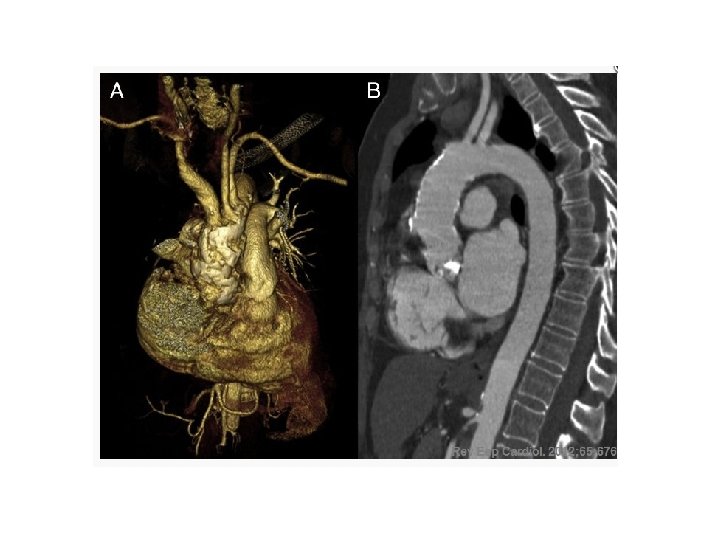

Our Patient • • • Not diabetic 2 Vessel CAD sparing the Left Main Syntax score NOT in the highest tertile Female Elderly Calcified aorta

Porcelain Aorta Kang M, Ha J. N Engl J Med 2012; 366: e 40.